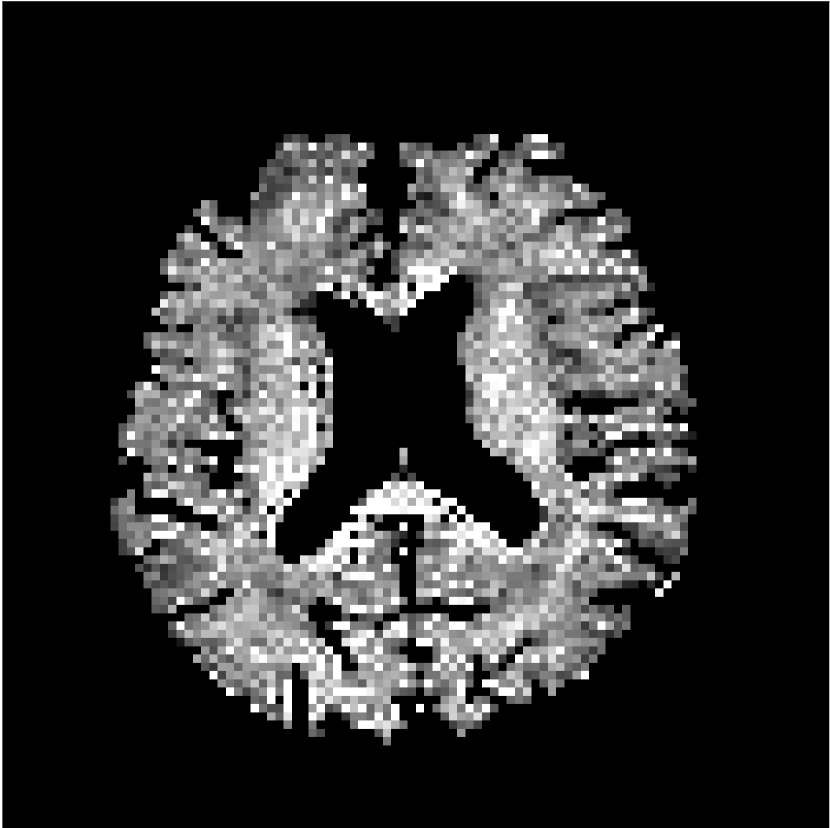

Figure 8 shows examples of non-diffusion-weighted images before and after processing. The raw images (Raw) served as the input for the magnitude deep learning (MCNN) and complex deep learning (CCNN) methods.

Raw 𝐱tsubscript𝐱𝑡\mathbf{x}_{t}

MCNN, fθ^(𝐱t)subscript𝑓^𝜃subscript𝐱𝑡f_{\hat{\theta}}\left(\mathbf{x}_{t}\right)

MCNN Resid., Ric(𝐱t)fθ^(𝐱t)Ricsubscript𝐱𝑡subscript𝑓^𝜃subscript𝐱𝑡\text{Ric}(\mathbf{x}_{t})-f_{\hat{\theta}}\left(\mathbf{x}_{t}\right)

CCNN, fθ^(𝐱t)subscript𝑓^𝜃subscript𝐱𝑡f_{\hat{\theta}}\left(\mathbf{x}_{t}\right)

CCNN Resid., Ric(𝐱t)fθ^(𝐱t)Ricsubscript𝐱𝑡subscript𝑓^𝜃subscript𝐱𝑡\text{Ric}(\mathbf{x}_{t})-f_{\hat{\theta}}\left(\mathbf{x}_{t}\right)

No PF

5/8 PF

Figure 8: Examples of non-diffusion-weighted images from in vivo data at b=0𝑏0b=0 s/mm2. Artifacts in the Raw image, 𝐱tsubscript𝐱𝑡\mathbf{x}_{t}, are corrected by the MCNN and CCNN models, fθ^(𝐱t)subscript𝑓^𝜃subscript𝐱𝑡f_{\hat{\theta}}(\mathbf{x}_{t}). Also shown are the residuals between the CNN corrections and the original Raw image with Rician bias correction Ric(𝐱t)Ricsubscript𝐱𝑡\text{Ric}(\mathbf{x}_{t}) [10]. The Gibbs artifacts removed by the methods are observed in the residuals. The MCNN method introduces some banding artifacts at the PF 5/8ths factor that are not present in the CCNN method.

Both methods remove artifacts, but the MCNN method allows residual rippling artifacts to pass through in the presence of partial Fourier. These rippling artifacts are not present in the CCNN method.